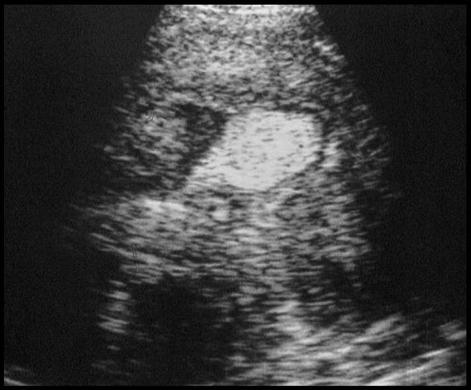

Cancer de l’endomètre